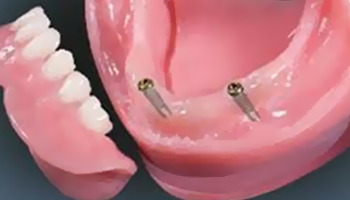

2개에서 4개 정도의 임플란트를 심고,

그 위에 딱 맞게 고정되는 틀니를 끼우는 방식입니다.

틀니 안쪽에 작은 고정장치가 있어

단추처럼 임플란트에 ‘딸깍’하고 끼워지는 구조라

일반 틀니보다 훨씬 덜 흔들리고 안정감이 좋습니다.